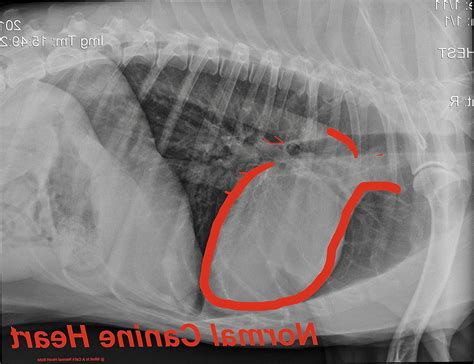

Understanding the health of our feline friends is crucial for their well-being, and one of the key indicators of a cat's health is their heart rate. The cat average heart rate can vary based on several factors, including age, activity level, and overall health. This blog post will delve into the intricacies of a cat's heart rate, how to measure it, and what to do if you notice any irregularities.

The cat average heart rate typically ranges between 140 to 220 beats per minute (bpm) for adult cats. Kittens, on the other hand, have a higher heart rate, which can be as high as 260 bpm. This higher rate is due to their smaller size and higher metabolic rate. As cats age, their heart rate tends to decrease slightly. It's important to note that these are general ranges, and individual cats may have slightly different heart rates.